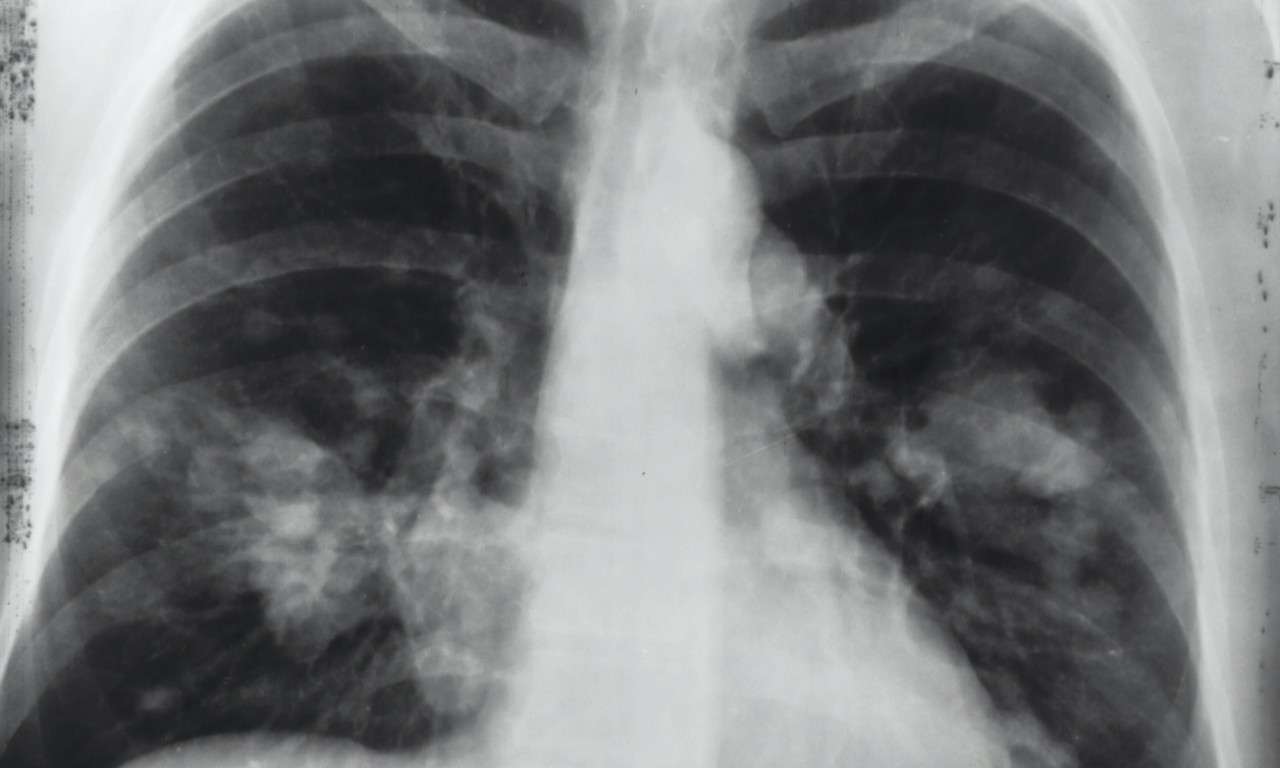

Od ove BOLESTI je umro BORA ĐORĐEVIĆ! DOKTORI objasnili koliko je opasna

Ova bolest predstavlja značajan problem u celom svetu, jer su njena učestalost i posledice u stalnom prastu

Frontmen grupe "Riblja čorba" hospitalizovan je zbog komplikacija uzrokovanih hroničnom obstruktivnom bolešću pluća

Frontmen rok grupe "Riblja čorba" priključen je na kiseonik zbog komplikacija izazvanih hronično obstruktivnom bolešću pluća